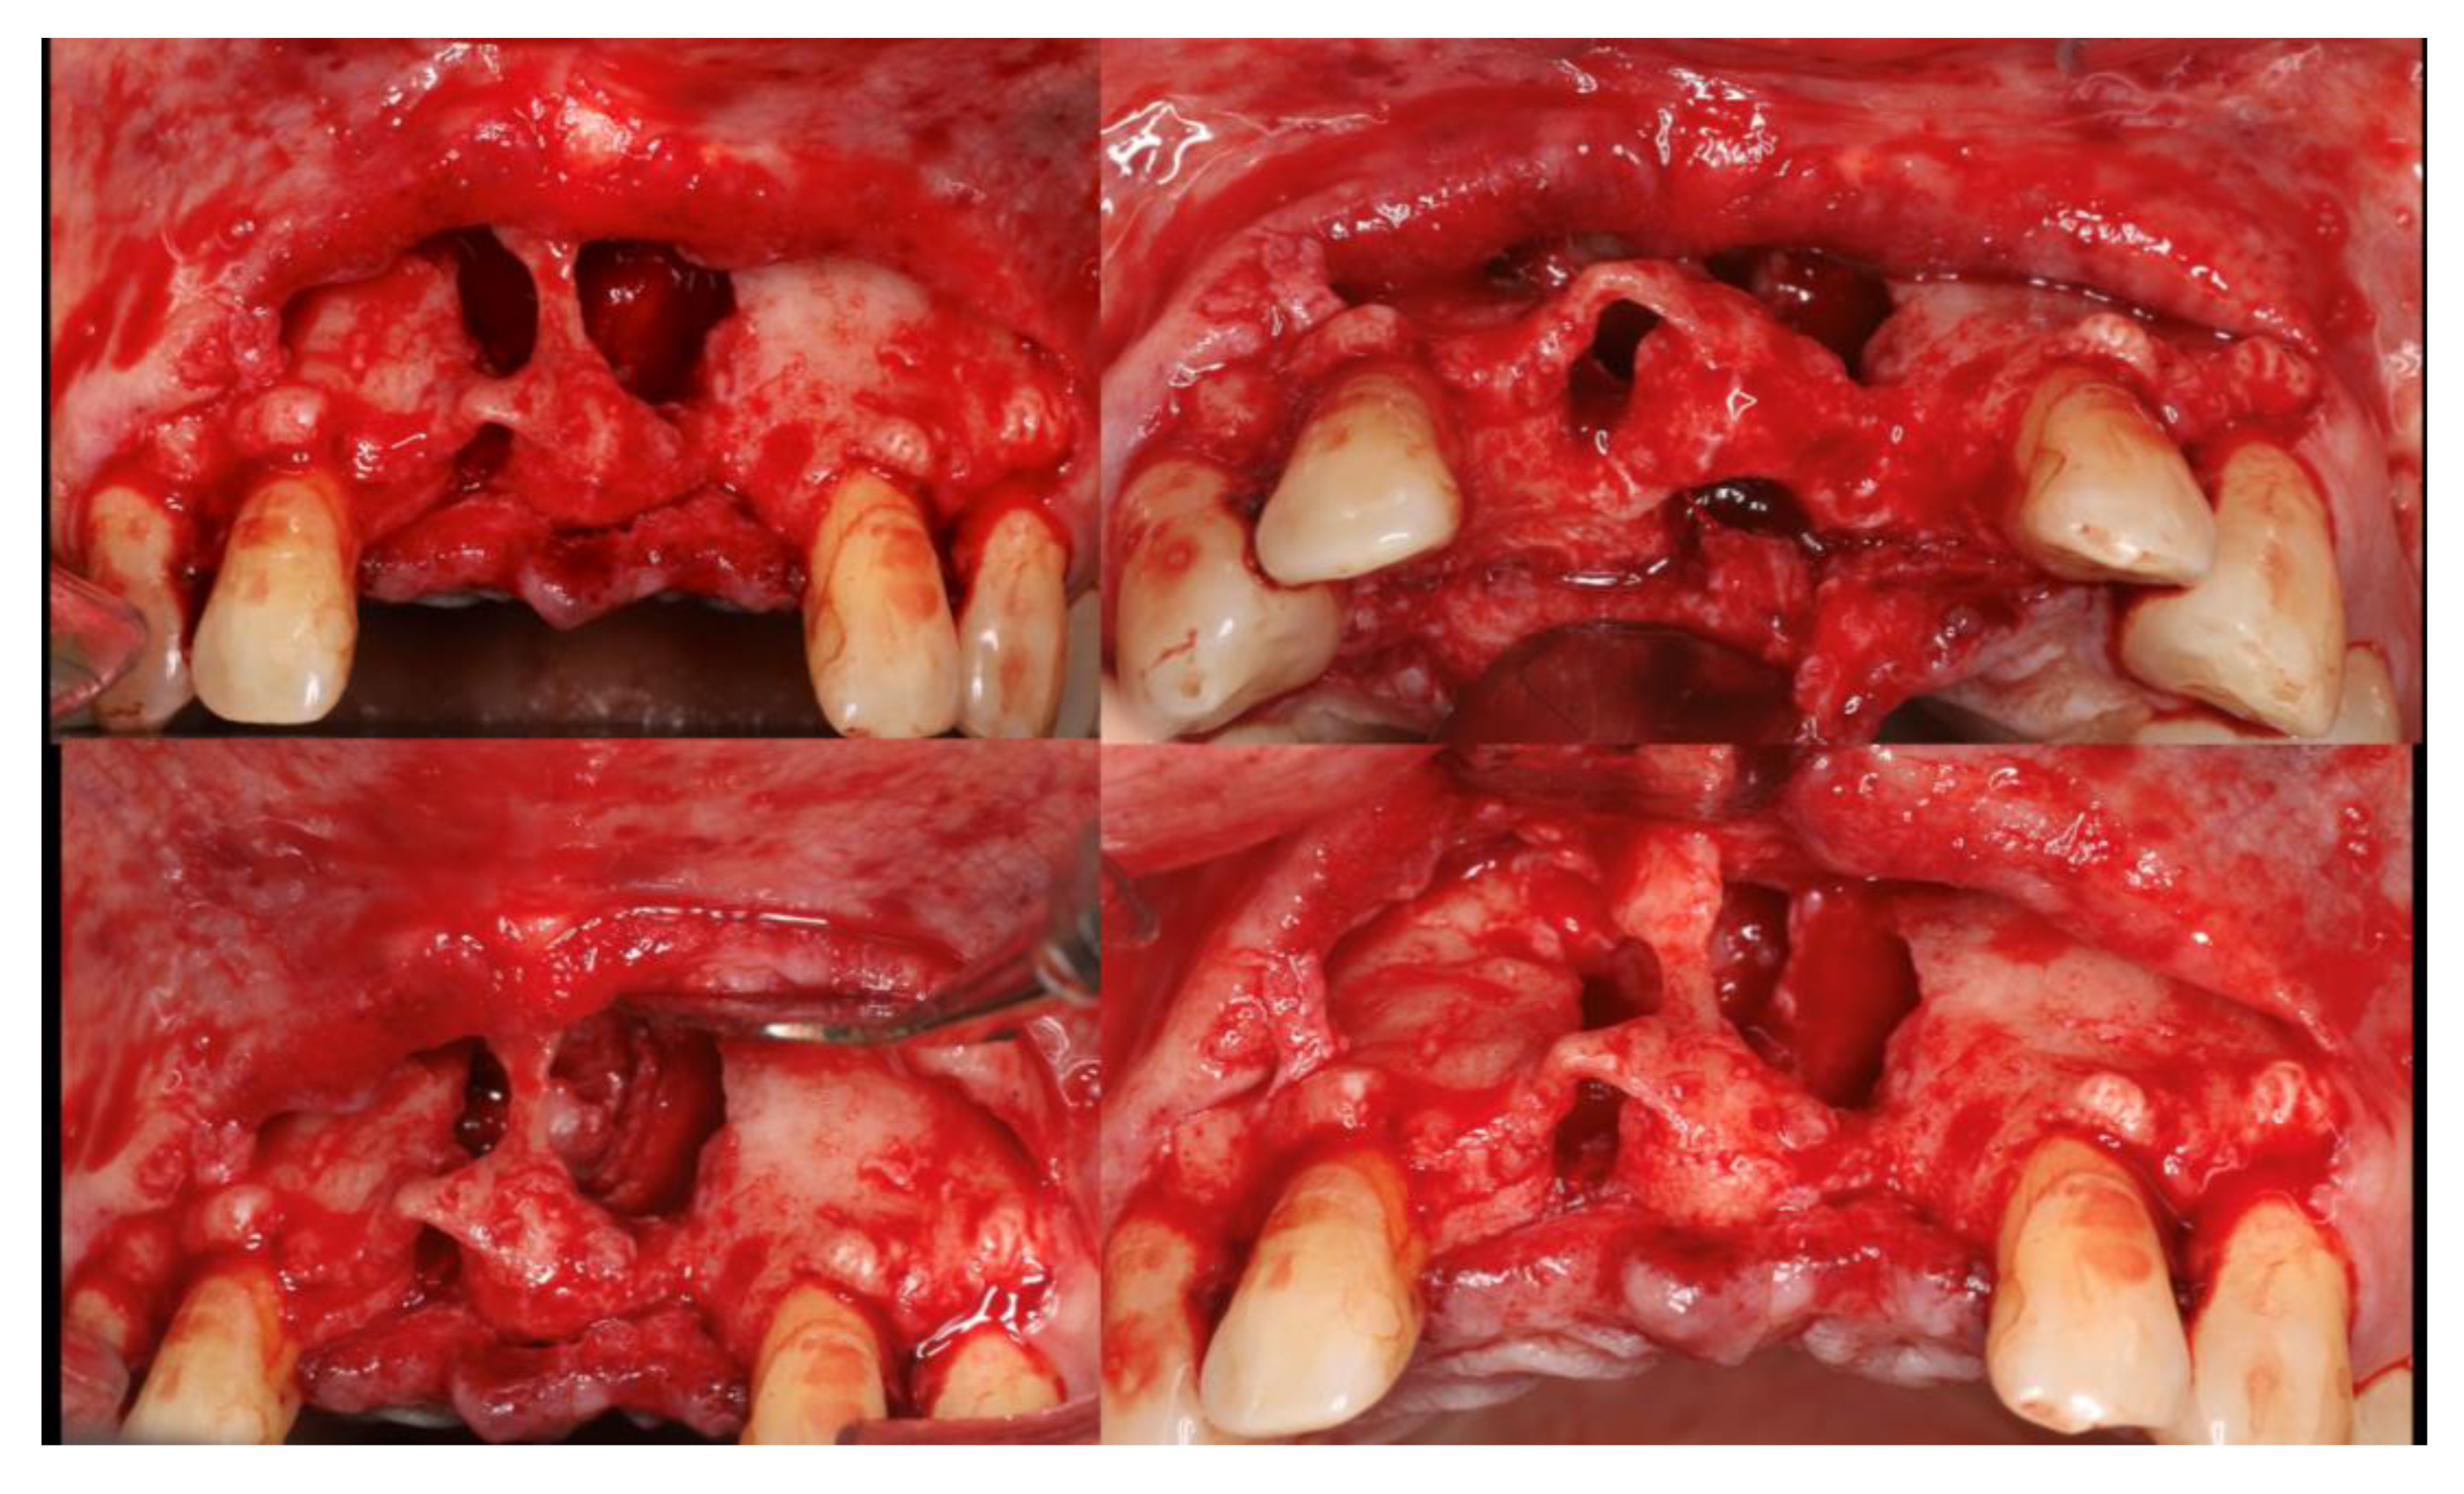

Figure 10. 18 months of follow-up – A -frontal view, B- occlusal view; C- periapical x-ray; D- patient smiling.

After 18 months is possible to observe a (Figure 10) aesthetic pleasant soft tissue architecture and a manutention of the bone volume achieve with the bone regeneration. No signs of reoccurrence of cyst were found.

In this clinical case with a follow up of 18 months, is possible to observe that bone volume reconstructed is stable and allowed an aesthetics result in terms of soft and hard tissue.

Radiographically, no reoccurrence of the odontogenic cyst was observed, being the enucleation successful.

The fence technique allowed the maintenance of the space that help to obtain a normal contour of the maxillary arch and aloud the dental implant placement.